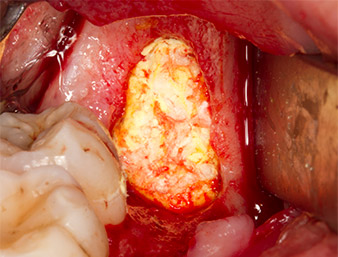

The tissue above the root remnant was not completely ossified and consisted for the most part of granulation tissue modified by inflammation (Fig. 4).

To obtain autogenous material for subsequent wound treatment, healthy bone chips were harvested from the surroundings of the root remnant with a piezo surgical instrument (Piezomed B5) (Fig. 5).

The autogenous tissue was removed with the scraper-shaped section of the working part of the instrument and stored in a physiological saline solution until further use (cf. Fig. 13).